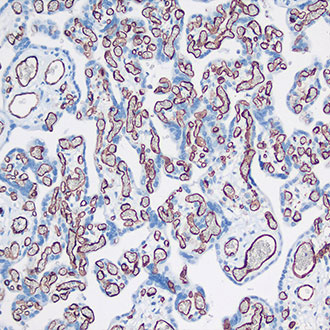

TTF-1

TTF-1 -